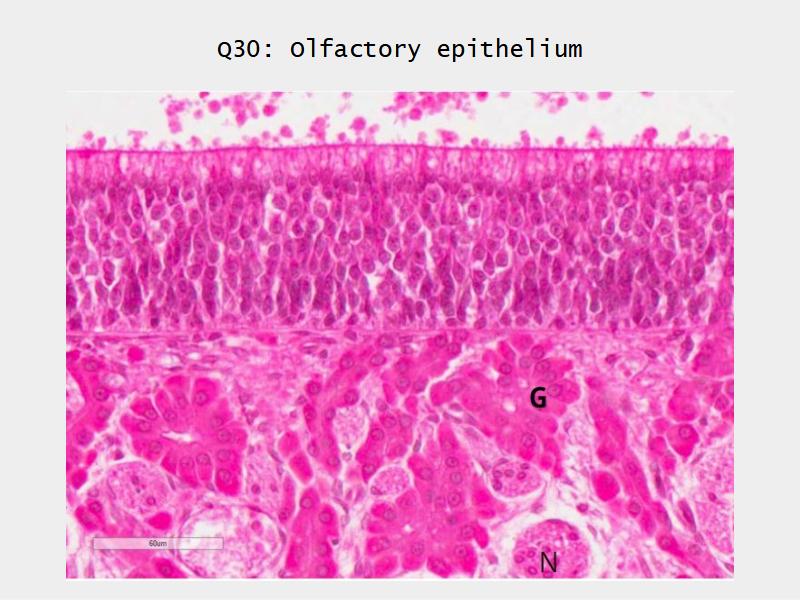

- Slide 108: Olfactory epithelium

Olfactory epithelium